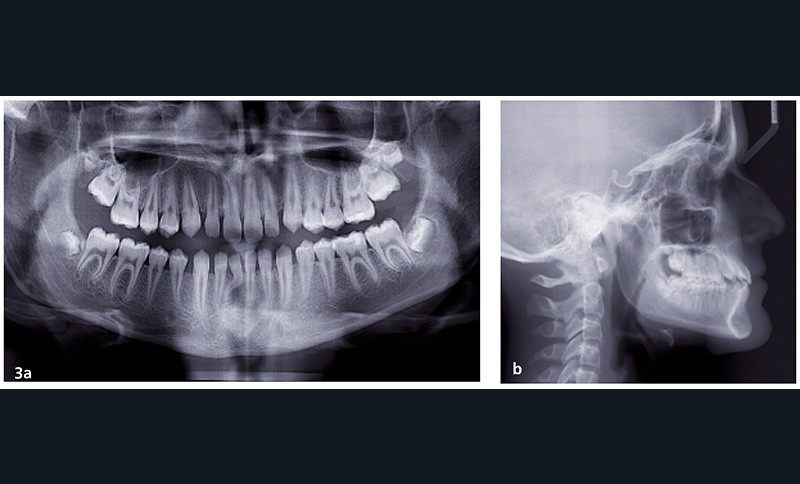

L’objectif est de rééquilibrer l’occlusion dentaire en réalisant des compensations dento-alvéolaires sans modifier le squelette. La chirurgie maxillo-faciale est écartée (fig. 3 et 4).